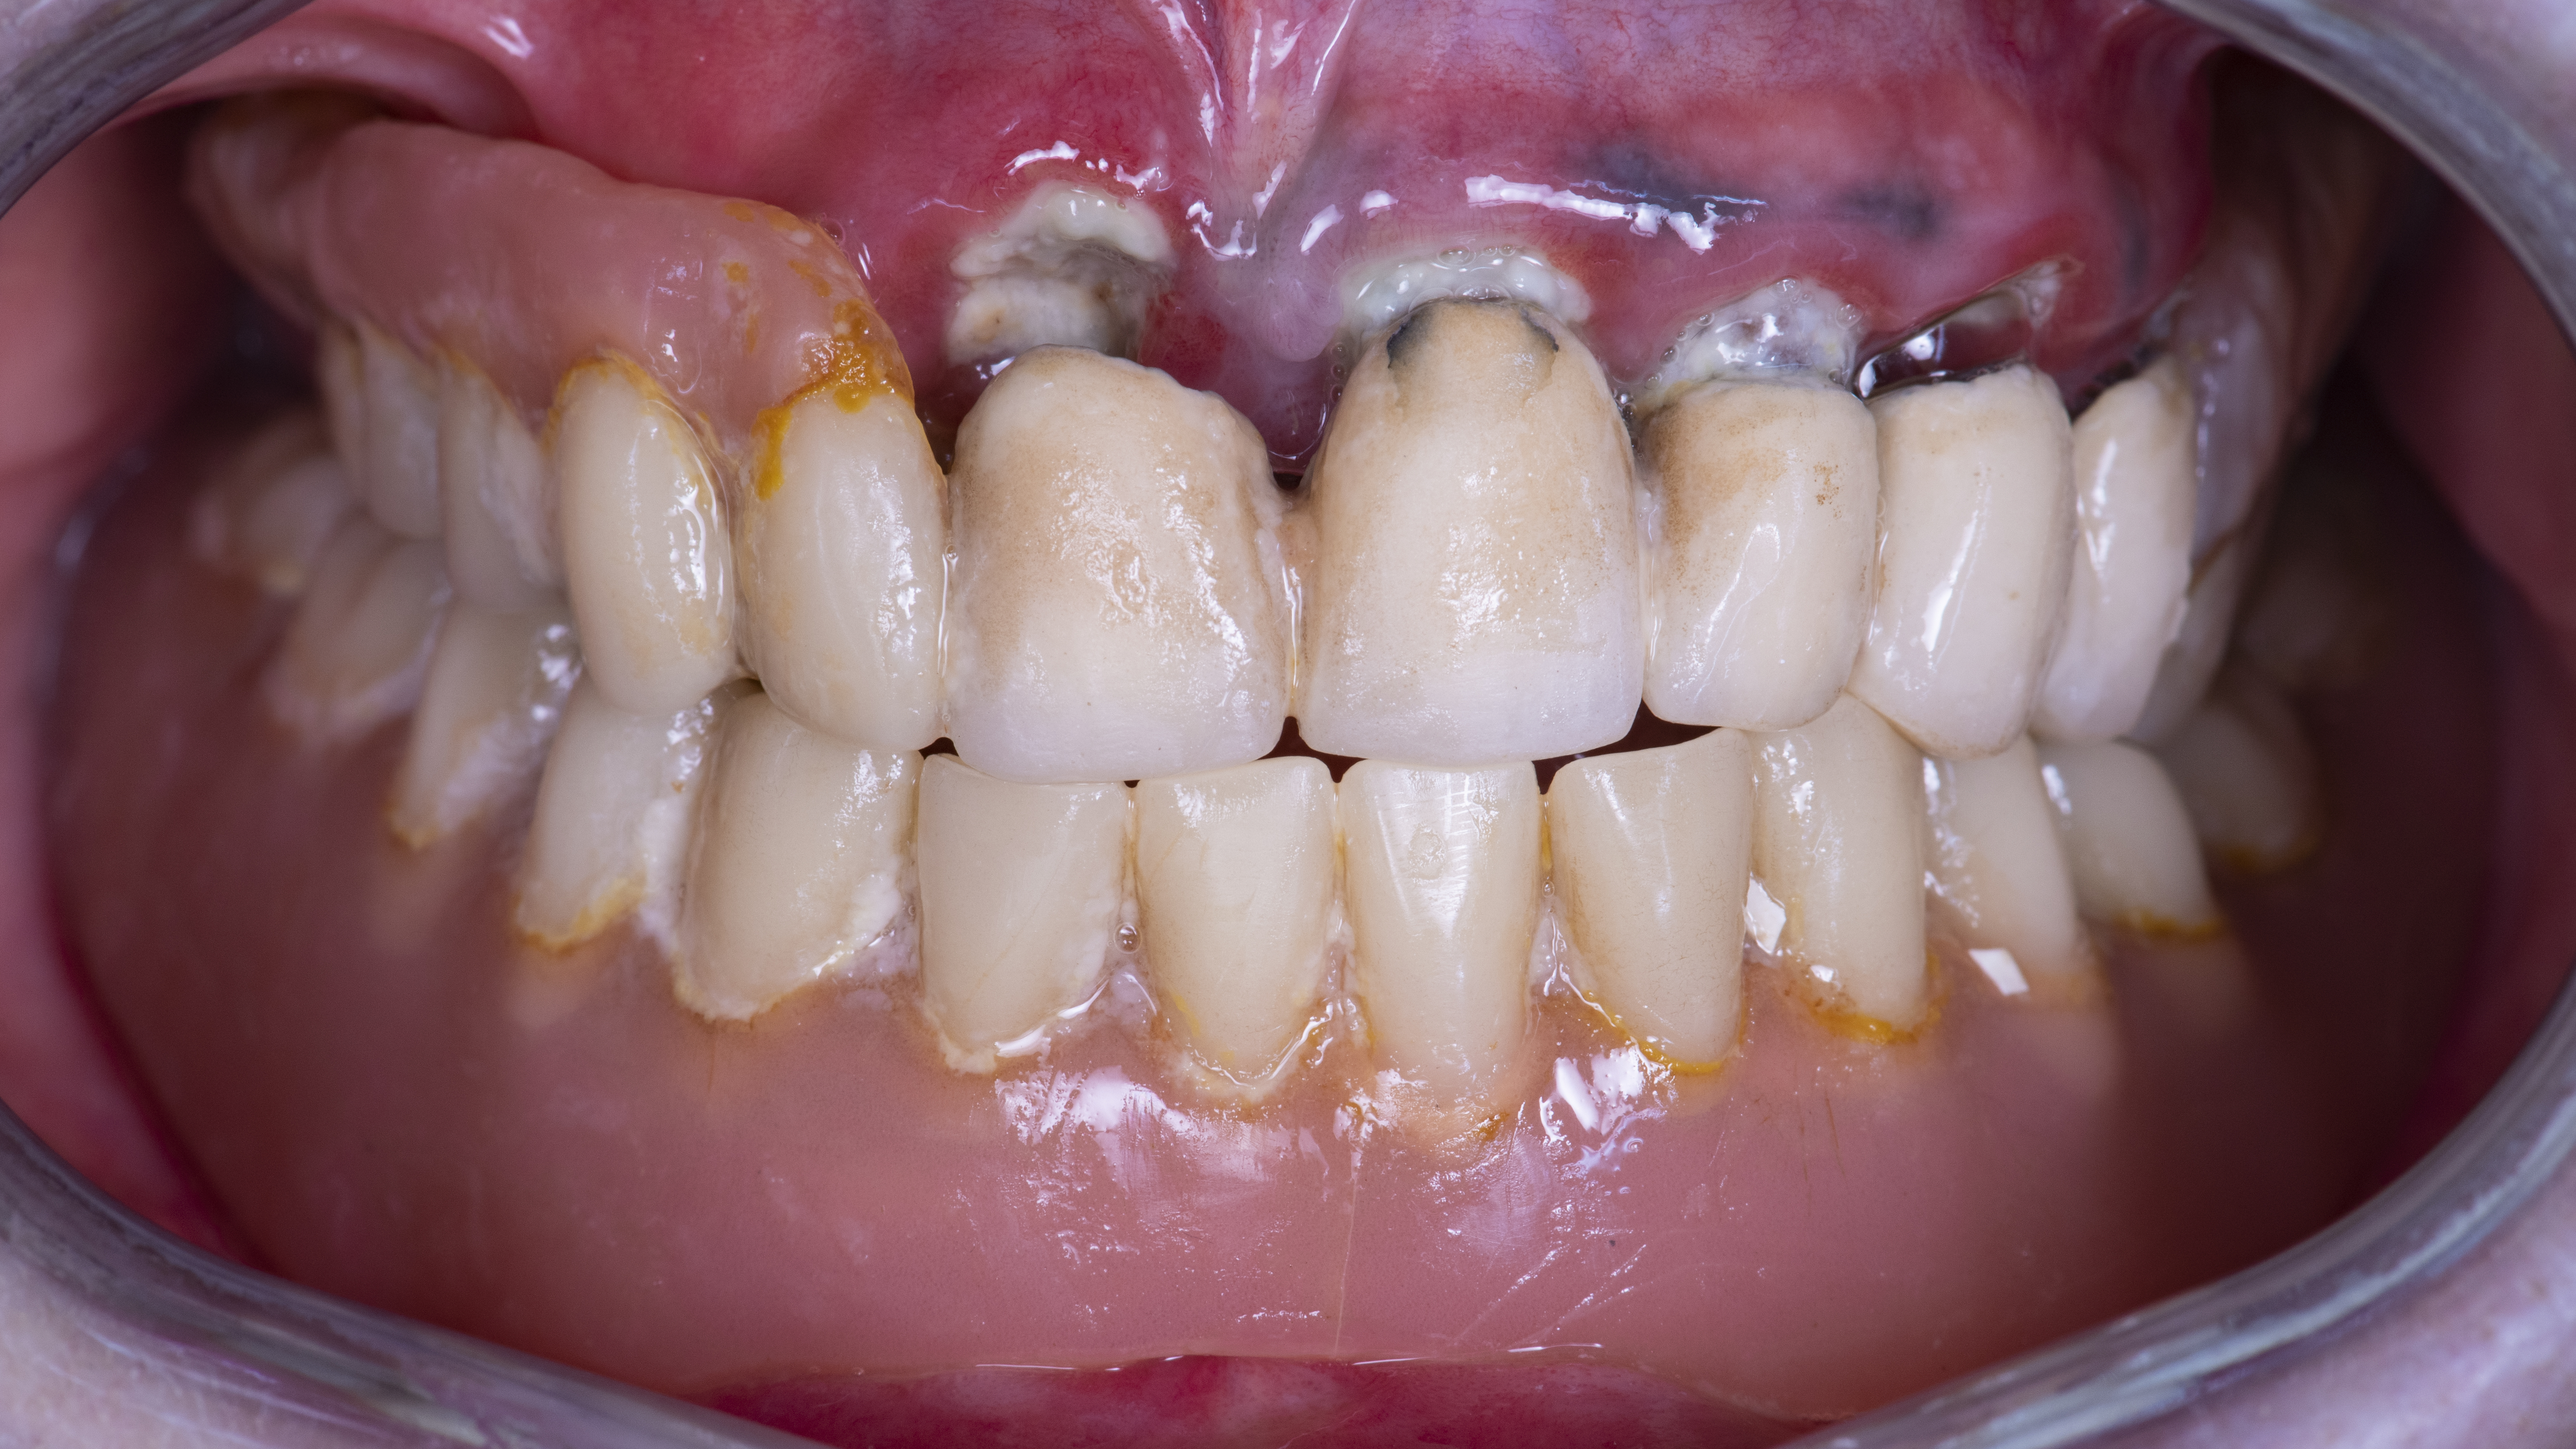

La paziente di 78 anni, in buono stato di salute generale, si presentava con una vecchia riabilitazione parziale rimovibile superiore supportata, tramite attacchi di precisione, da una protesi fissa che aveva ormai perso la sua stabilità posizionale a causa della grave compromissione degli elementi dentali. L’arcata inferiore era riabilitata tramite protesi totale rimovibile ormai incongrua (Fig. 1, 2).

Fig. 2. Situazione iniziale aspetto intraorale